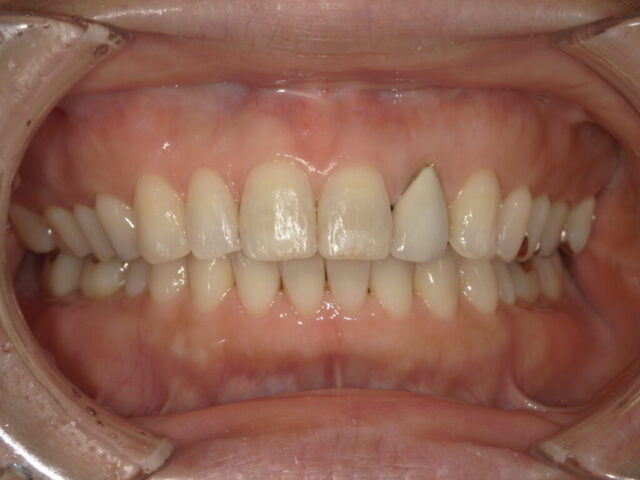

過蓋咬合(深い噛み合わせ)の改善

成人矯正

| 診断名 | 過蓋咬合 / 下顎前歯の先天欠如 |

|---|---|

| 治療期間・回数 | 2年5ヵ月 |

| 治療方法 | ワイヤー矯正(上顎4番 抜歯) |

| 費用 | 825,000円(税込) |

| デメリット・注意点 | 治療初期は痛みが生じる場合がありますが、約1週間で慣れていただけます。 |